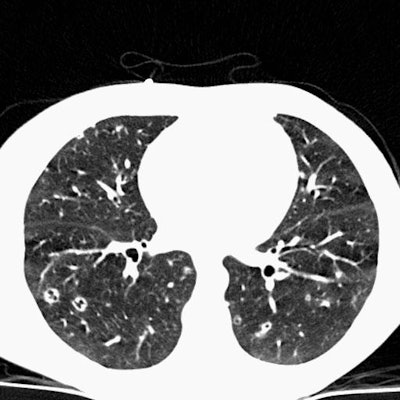

Scott WilliamsThoracic ImagingAutoimmuneAutoimmune > EG > Images > Case3Scott WilliamsApr 2, 2002 Eosinophilic Granuloma Case 3: In this example of pulmonary eosinophilic granuloma. Computed tomography of the chest demonstrated multiple thin walled cysts, cavitating nodules, and scattered non-cavitary nodules. Latest in AutoimmuneAutoimmune > Hyalinizing granulomaOctober 19, 2020Autoimmune > DrugsOctober 19, 2020Autoimmune > DrugsMarch 12, 2018Autoimmune > EG > Images > Case5July 31, 2011Related StoriesAutoimmuneAutoimmune > Lymphomatosis > Images > Case1AutoimmuneAutoimmune > Sarcoid > Images > Sarcoid7AutoimmuneAutoimmune > IPFibrosis > UIPimages > Case1AutoimmuneAutoimmune > Sarcoid > Images > Sarcoid1B